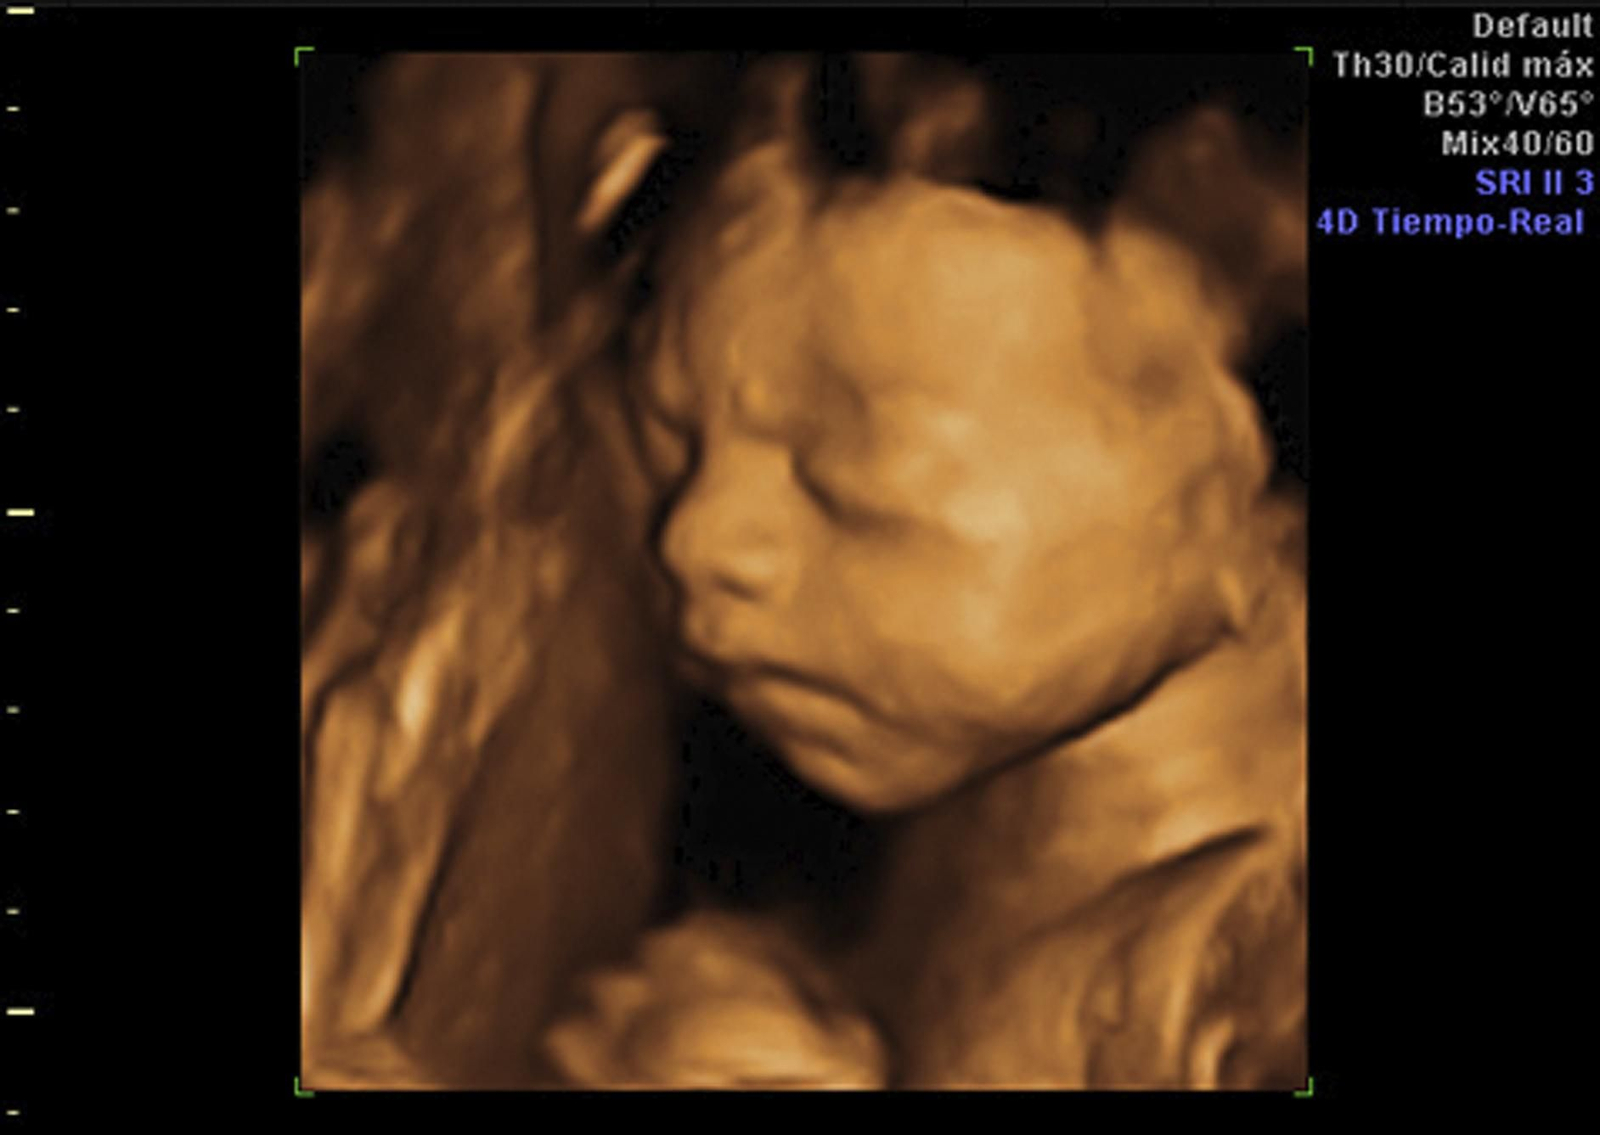

Una ecografía 4D.

Una ecografía 4D. / Quirónsalud Campo De Gibraltar

Los adelantos tecnológicos han permitido grandes avances en el diagnóstico fetal. Los equipamientos actuales permiten captar detalles en el interior del útero con sorprendente precisión. Son imágenes en las que el especialista puede apreciar incluso el movimiento del bebé en el entorno amniótico con tal exactitud que el Ginecólogo recibe una visión extraordinaria del desarrollo del feto.

Sin duda, la madre que espera a su bebé así como su entorno familiar marcan en el calendario el día en que tienen oportunidad de ver la cara de su bebé en imagen tridimensional y en movimiento. En este aspecto, el factor emocional es un componente intrínseco para las familias que están pasando por la dulce etapa de la espera de un nuevo integrante en la familia.

Para el especialista el momento en que ven por primera vez la cara de sus hijos de forma tan definida “es muy emocionante y para nosotros un privilegio ser testigos de ello. La imagen que reciben es en 3D en la que se pueden apreciar con nitidez los gestos del bebé. Es un momento muy especial en el que se refuerza aún más si cabe el vínculo materno”.